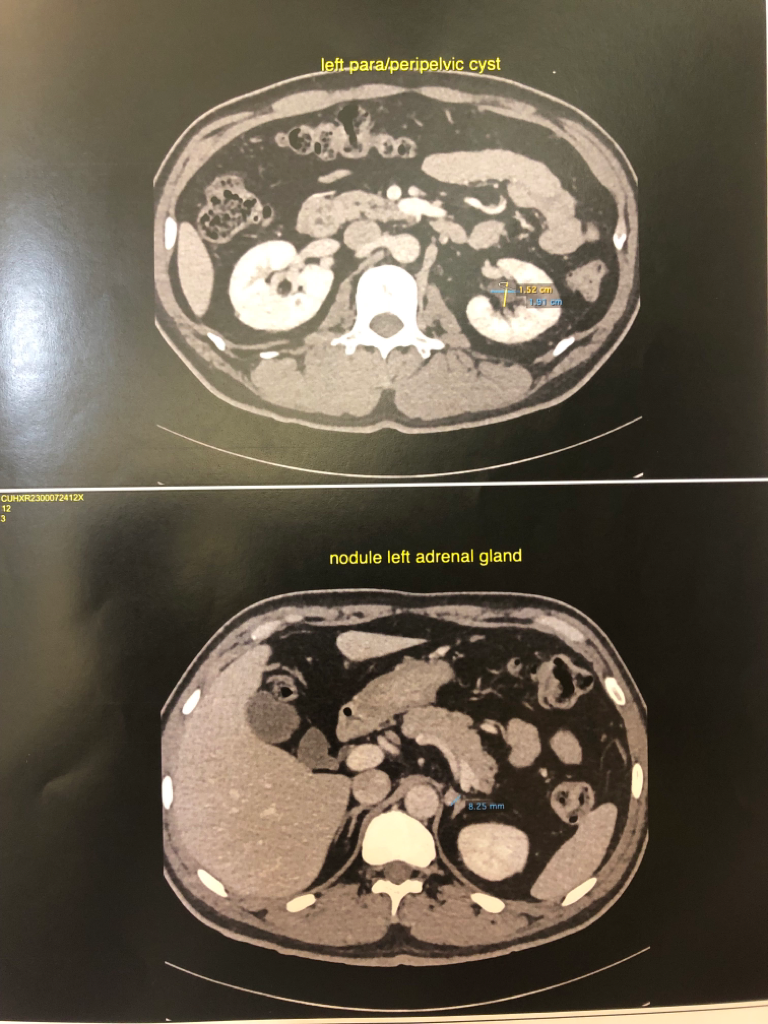

양쪽 부신에 낭종이 있고, 신장에 결석인지 물혹인지가 있고 폐 석회화,경증의 전립선 비대 등등이 있다고 알고 있는데요

• 1번 째 사진

• 2번 째 사진